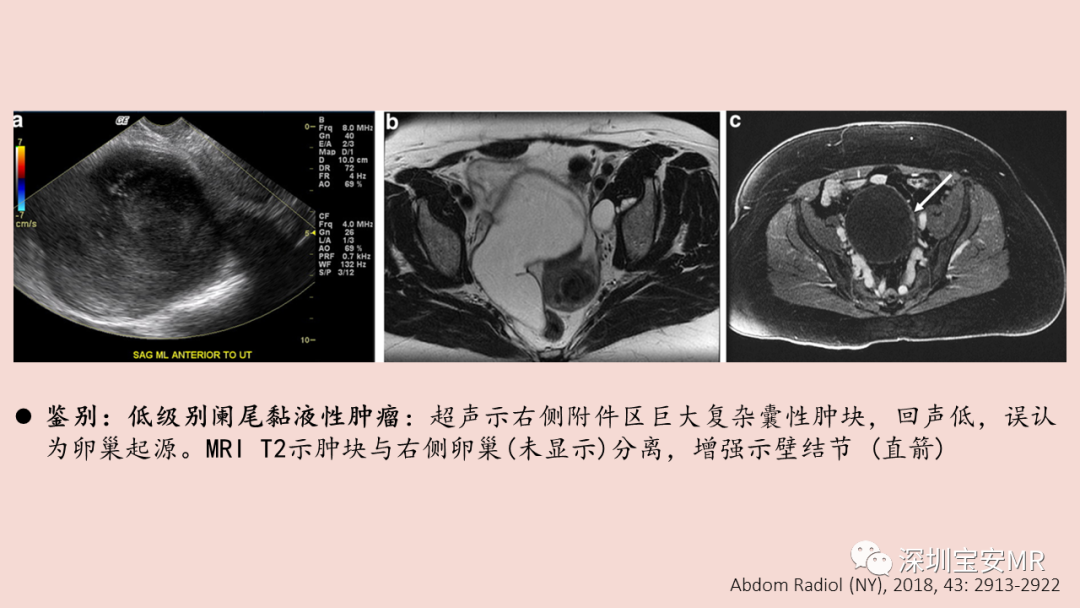

图片